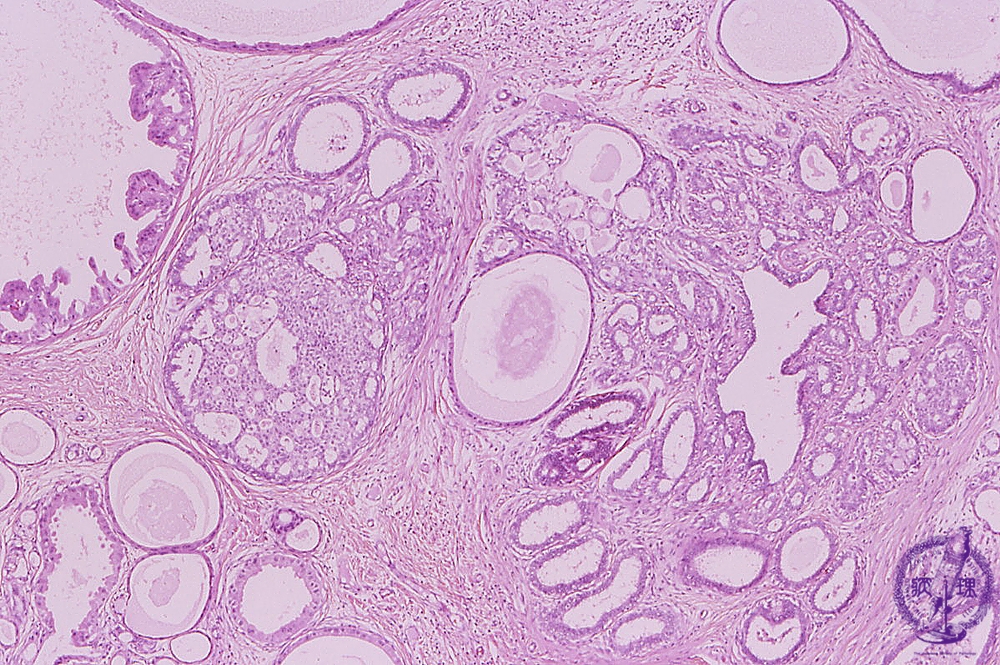

- 14.Breast

- (1)Mastopathy

Microscopic image(HE stain, low power view):Mastopathy is typically represented by a non-inflammatory/neoplastic lesion. Typically hormonal abnormalities are thought to be involved. Characterized by the concomitant proliferative and degenerative changes such as cyst formation, ductal hyperplasia, and sclerosing adenosis.